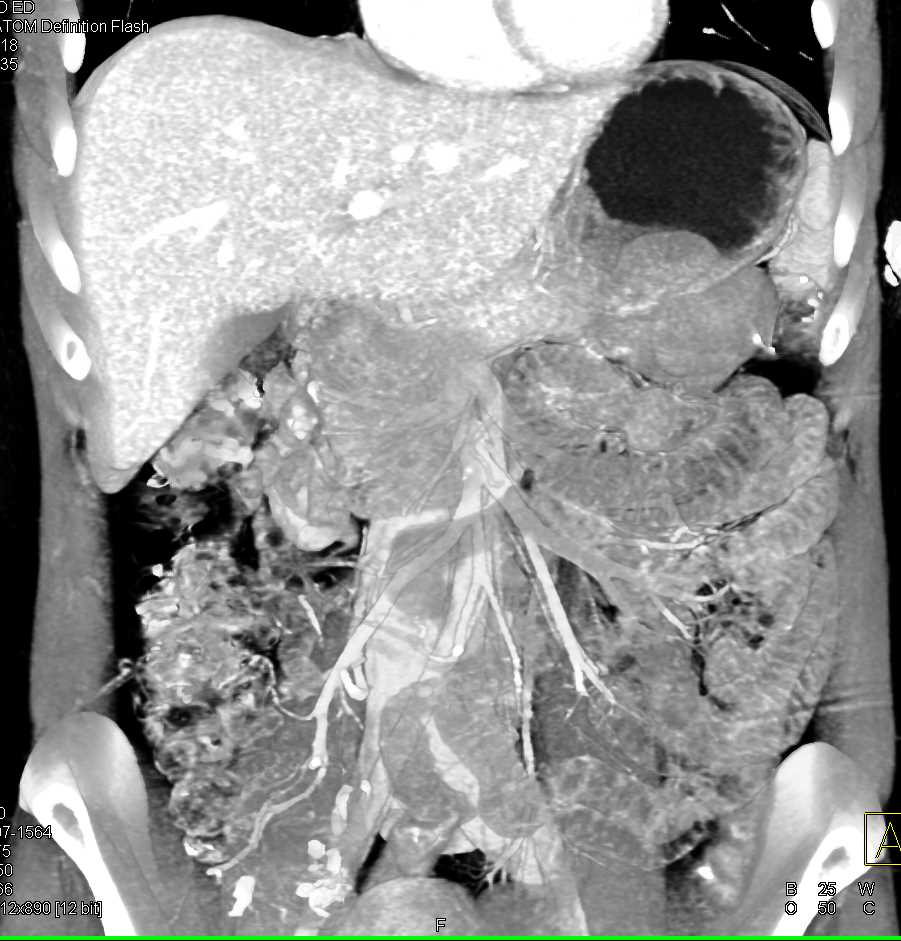

Mass Pushes on Tail of Pancreas was Ganglioneuroma